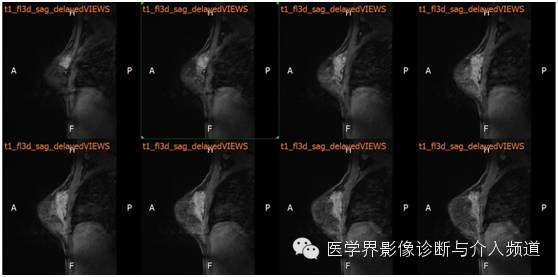

MR平扫及增强示:双乳表面皮肤光整,乳头无凹陷,皮下层次清晰,双乳腺体较丰富,右乳外上象限近胸壁处可见不规则样团状等T1异常信号,FS-T2WI呈高信号,DWI(b=800)示病灶呈略高信号,ADC图呈略低信号,边界不清,并沿导管浸润,范围约4.8×2.5×6.6 cm,双乳内见多发片状、结节样等T1略长T2异常信号。注入GD-DTPA后,上述病灶强化呈”平台”型。右侧胸骨后及腋窝见多发淋巴结影,较大者位于右侧腋窝,最大径约0.8 cm。